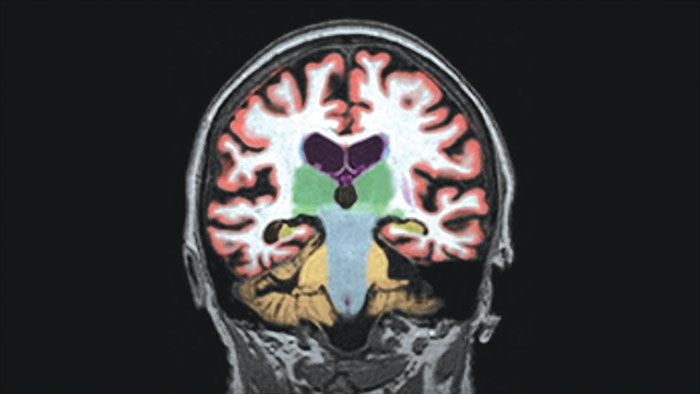

MR Longitudinal Brain Imaging (LoBI)

Gain an optimized view of the body’s most complex organ

Supports the visualization of brain images for the evaluation and monitoring of changes across multiple time points. The application performs automatic registration between studies and provides semi-automatic segmentation and editing tools for volumetric measurement of brain lesions.

• The Comparative Brain Imaging feature uses bias field-correction, intensity scaling, image registration and mathematical subtraction to provide color-coded images highlighting subtle brain changes over time.

Automated brain image analysis solutions

MR NeuroQuant®* automatically segments and measures volumes of brain structures and compares these volumes to standard norms.

• Convenient and cost-effective means to gain reliable, objective measurements of neurodegeneration.

• Helps reduce the subjectivity of the diagnosis.